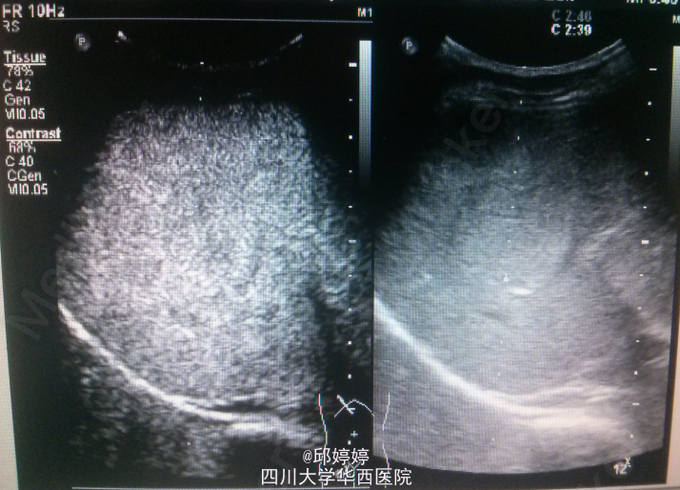

患者,男,36岁,体检超声发现肝内数个稍强回声团,较大位于右后叶,大小约5.0x3.7cm,上述团块边界清楚,形态较规则,较大者推挤右肝静脉,部分内部回声呈网格状;超声造影:团块动脉期呈环状结节样高增强(图1),门脉期持续向内充填(图2),实质期呈等增强(图3)。 讨论:血管瘤典型的超声造影表现特点明显,易于与其他良性或恶性病变相区分。